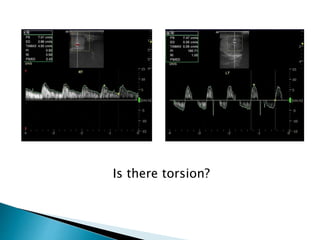

Is there torsion?

 Doppler ultrasoundwith sensitivity of 85% in the diagnosis of torsion reduced vascularity (absence or poor colour flow, reduced peak systolic velocities) compared with the unaffected side.  Given the importance of operating within a few hours of the onset of symptoms  Neither the performance nor interpretation of an ultrasound examination should delay surgical treatment.  If there is doubt the urologist should operate on clinical grounds

 Doppler ultrasound with sensitivity of 85% in the

diagnosis of torsion reduced vascularity

(absence or poor colour flow, reduced peak

systolic velocities) compared with the unaffected

side.